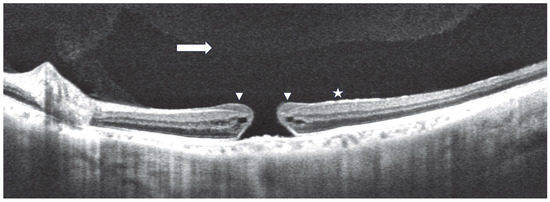

Figure 1

Background/Objectives: To propose a combined surgery of surgically induced macular detachment (MD) and autologous internal limiting membrane (ILM) transplantation to treat refractory full thickness macular holes (FTMHs). Methods: A series of patients affected by refractory FTMHs underwent a combined surgery. The [...] Read more.

Background/Objectives: To propose a combined surgery of surgically induced macular detachment (MD) and autologous internal limiting membrane (ILM) transplantation to treat refractory full thickness macular holes (FTMHs). Methods: A series of patients affected by refractory FTMHs underwent a combined surgery. The following demographic and clinical data were collected: age, gender, eye, lens status, and best corrected visual acuity (BCVA). The tomographic pre- and post-operative parameters were the following: pre-operative FTMH diameter, refractory FTMH morphology (flat/with cuff), FTMH closure, foveal profile (regular/flat/inverted), flap displacement, and outer retinal layers restoration. Results: The study included a total of 14 pseudophakic eyes (14 patients). In all of the patients, surgical FTMH closure was reached. The mean BCVA improved after surgery from 1.1 ± 0.14 to 0.48 ± 03 logMAR (p < 0.0001). Statistical analysis demonstrated that the larger the FTMH, the poorer the post-operative gain in BCVA (p −0.5). The post-operative regular foveal profile was obtained in 50% of the eyes with a mean post-operative BCVA of 0.3 logMAR. A negative correlation between the time interval from diagnosis to surgery and post-operative BCVA gain was highlighted (p −0.8). Conclusions: The proposed combined surgical technique led to encouraging anatomical and functional results. Surgically induced MD increased the elasticity of the retina, and the free flap isolated the macular hole from the vitreous chamber favoring its closure. Full article